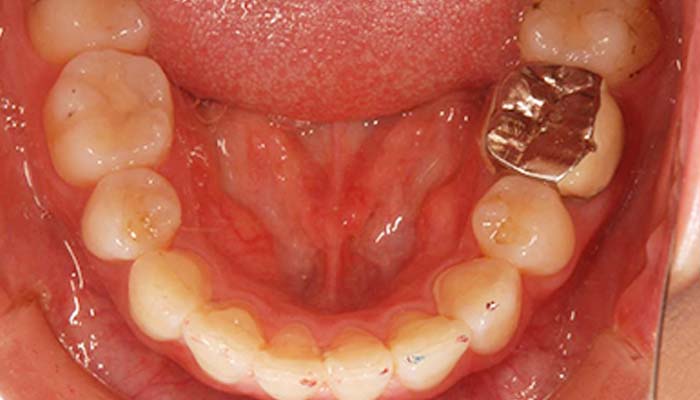

上顎 治療前

年齢・性別 | 12歳・女性 |

---|---|

主訴 | 歯並びが気になる |

治療内容 | ワイヤー矯正 |

費用 | ワイヤー矯正 ¥420,000 |

期間 | 1年半 |

副作用・リスク | しみたり、違和感を感じたりすることが あります。 |

担当者所見 | 矯正治療を希望されて来院しました。 来院時は右上4番の真下に右上5番があり、 生えてくるスペースが全くない状態でした。 ワイヤー矯正治療にて、抜歯することなく 正常咬合に治療でき、右上5番も正常に生えてきました。 |